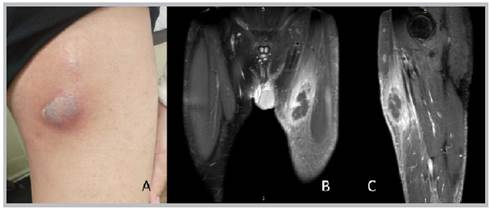

Figure 1 A: a photograph of the anterior internal aspect of the left thigh showing an abscess in the vertex of Scarpa's triangle. B: magnetic resonance imaging, coronal section, C: sagittal section showing an abscess and area of pyomyositis in the left thigh..